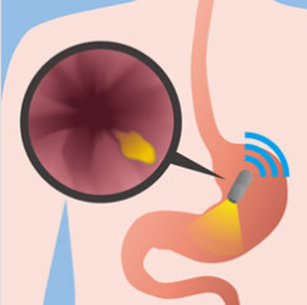

Εκτός από τις αιματολογικές εξετάσεις, ο υπόλοιπος παρακλινικός έλεγχος είναι άκρως απαραίτητος, για να μπορέσει ο γιατρός να διαγνώσει με βεβαιότητα τη νόσο και να διαπιστώσει την έκταση της. Η κολονοσκόπηση σκοπό έχει να αξιολογήσει την κατάσταση της εσωτερικής επένδυσης του παχέος εντέρου, καθώς και του τελευταίου τμήματος του λεπτού εντέρου, δηλαδή του τελικού ειλεού.

Κολονοσκόπηση

Το κολονοσκόπιο είναι ένα μακρύς, λεπτός και ευέλικτος σωλήνας, που προωθείται μέσω του πρωκτού και παρέχει μεγεθυμένες εικόνες του παχέος εντέρου. Πρόκειται για μία εξέταση που εκτελείται πολύ συχνά σε εξωτερική βάση καθώς προκαλεί ήπια έως ελάχιστη ενόχληση, χωρίς να απαιτείται νοσηλεία του ασθενούς ακόμα και αν συνοδεύεται από ενδοσκοπική αφαίρεση πολυπόδων που εντοπίζονται κατά τη διάρκεια της κολονοσκόπησης. Σε ορισμένες περιπτώσεις ο γιατρός θα προτρέψει τον ασθενή να υποβληθεί και σε μία γαστροσκόπηση. Ένα ενδοσκόπιο εισάγεται από το στόμα προκειμένου να ελεγχθούν ο οισοφάγος, το στομάχι και το πρώτο τμήμα του λεπτού εντέρου. Και οι δύο αυτές εξετάσεις επιτρέπουν στο γιατρό να απεικονίσει άμεσα την εσωτερική επένδυση του εντέρου (του βλεννογόνου), λαμβάνοντας ταυτόχρονα δείγματα ιστού για να εκτιμηθούν παθολογοανατομικά, δηλαδή να γίνουν βιοψίες από πάσχουσες περιοχές του βλεννογόνου. Εάν κριθεί απαραίτητο, εντοπισμένες στενώσεις του εντέρου που προκαλούν απόφραξη και συμπτώματα στον ασθενή μπορεί να αντιμετωπιστούν με ενδοσκοπικές διαστολές, οι οποίες ολοκληρώνονται μέσα από το κολποσκόπιο, εφόσον, βέβαια ο γαστρεντερολόγος που εκτελεί την κολονονοσκόπηση διαθέτει την απαραίτητη εμπειρία.

Ειδικά για την εκτίμηση της προσβολής του λεπτού εντέρου, το οποίο δεν είναι εύκολα προσβάσιμο με ενδοσκοπικές μεθόδους, σήμερα χρησιμοποιείται η ασύρματη ενδοσκοπική κάψουλα, η οποία είναι μία κάψουλα, που έχει ενσωματωμένη μία μικρή βιντεοκάμερα συνεχούς καταγραφής, οπότε, μετά την κατάποση της από τον ασθενή, λαμβάνονται χρήσιμες πληροφορίες από τη μικρο-βιντεοσκόπηση του βλεννογόνου του λεπτού εντέρου.

Ενδοσκοπική κάψουλα